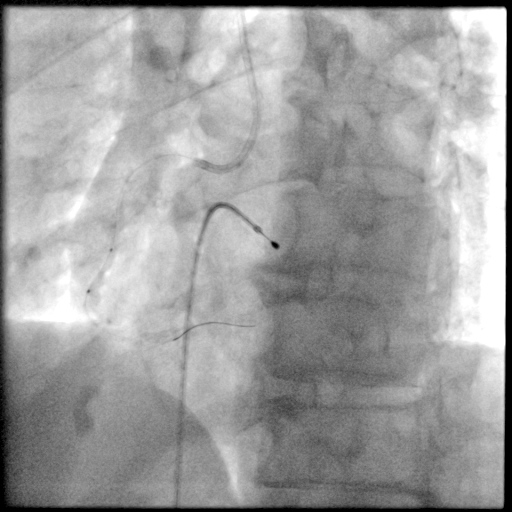

冠脉造影

PCI过程-球囊PTCA

预置临时起搏器后,7F AL1.0无法到位,更换为7F SAL1.0至RCA开口,应用非顺应性球囊2.5X15mm,于RCA中段病变处以12-18atm扩张,球囊膨胀不佳。